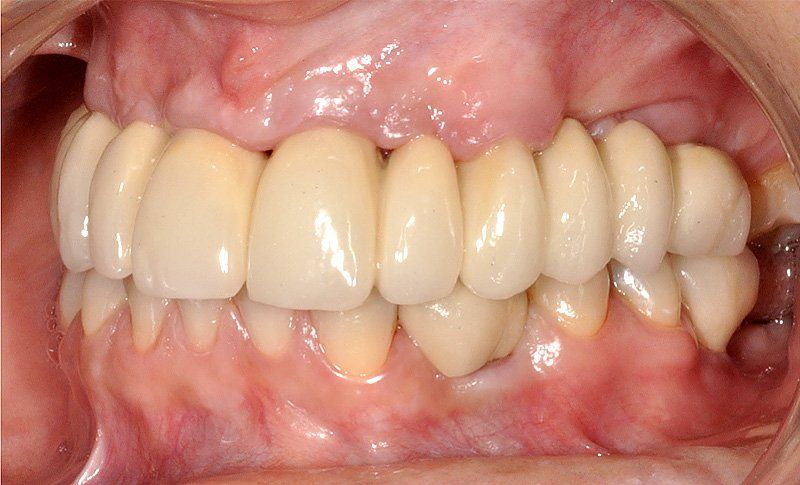

Sus beneficios son que se instalan con mayor tranquilidad para usarlos, no hay que sacárselo todas las noches, la gente queda con una mayor seguridad interna, mejora la autoestima, el humor y las relaciones interpersonales.

¿Por qué la gente debería hacerse el tratamiento en Clínica Dental Sonríe?

Porque se hace en pabellones certificados por la Universidad de Chile. Son dependencias hechas única y exclusivamente para hacer intervención en sitios estériles. También se hace más cómodo y se pasa rápido el periodo de espera. Del momento en que se insertan los implantes debe transcurrir un período de tiempo de entre 4 a 6 meses si es en mandíbula o maxilar superiores respectivamente para que el tejido óseo cicatrice y logre integrarse a la superficie del implante